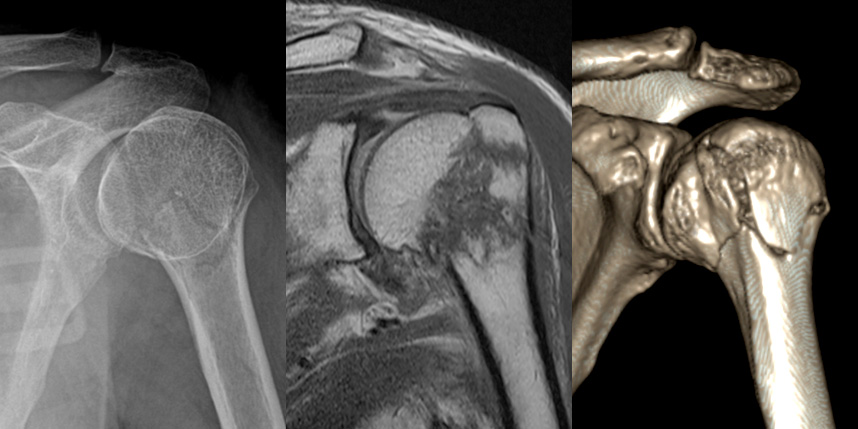

상완골 골절

골절은 정확하게 골절편을 잘 맞추고 고정하는 것이 중요합니다. 특히 관절면을 잘 맞추는 것이 중요합니다.

감탄정형외과는 정확한 초기 진단을 통해 골절 발생일로부터 최대한 빨리 원래의 뼈 상태에 가깝게 원복시키고,